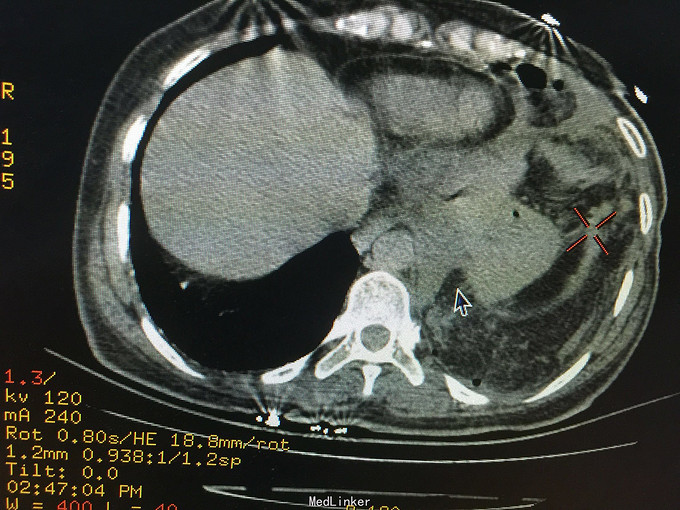

女,41岁, 主诉:腹部胀痛伴不排便、不排气1周, 现病史:一周前无诱因开始腹部胀痛,逐渐加重,以左上腹明显,不排便,不排气,恶心,呕吐数次胃内容物,在当地医院抗炎治疗不见好转,今排腹部平片诊断为“肠梗阻”,来诊。

一般状态可,腹部平坦,未见肠型及蠕动波,脐周压痛,左上腹明显,无腹肌紧张,未及包块,移动性浊音阳性,肠音2次/分。 辅助检查:全腹CT:腹部肠管明显扩张,积液,左侧膈肌局部缺损,腹腔内肠管及系膜组织疝入胸腔。

诊断:膈肌疝,疝内容嵌顿,肠梗阻 处理:手术治疗。